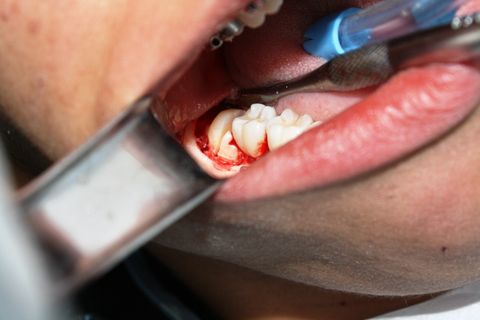

Exodontia 18 e 48

Caso clínico, 01 de Ago de 2014

Paciente AB, sexo feminino, 19 anos, com indicação para exodontia dos elementos 18 e 48 incluso e mesio-incliniado.

Fotos do caso